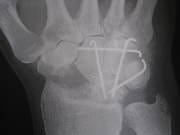

本日、ドクターにお願いしてオペ直前のレントゲンをゲットしましたので

お見せいたします。

1枚目オペ前日 2枚目オペ直後 3枚目昨日 いかがですか?

骨の写真ばっかりですみません(汗)